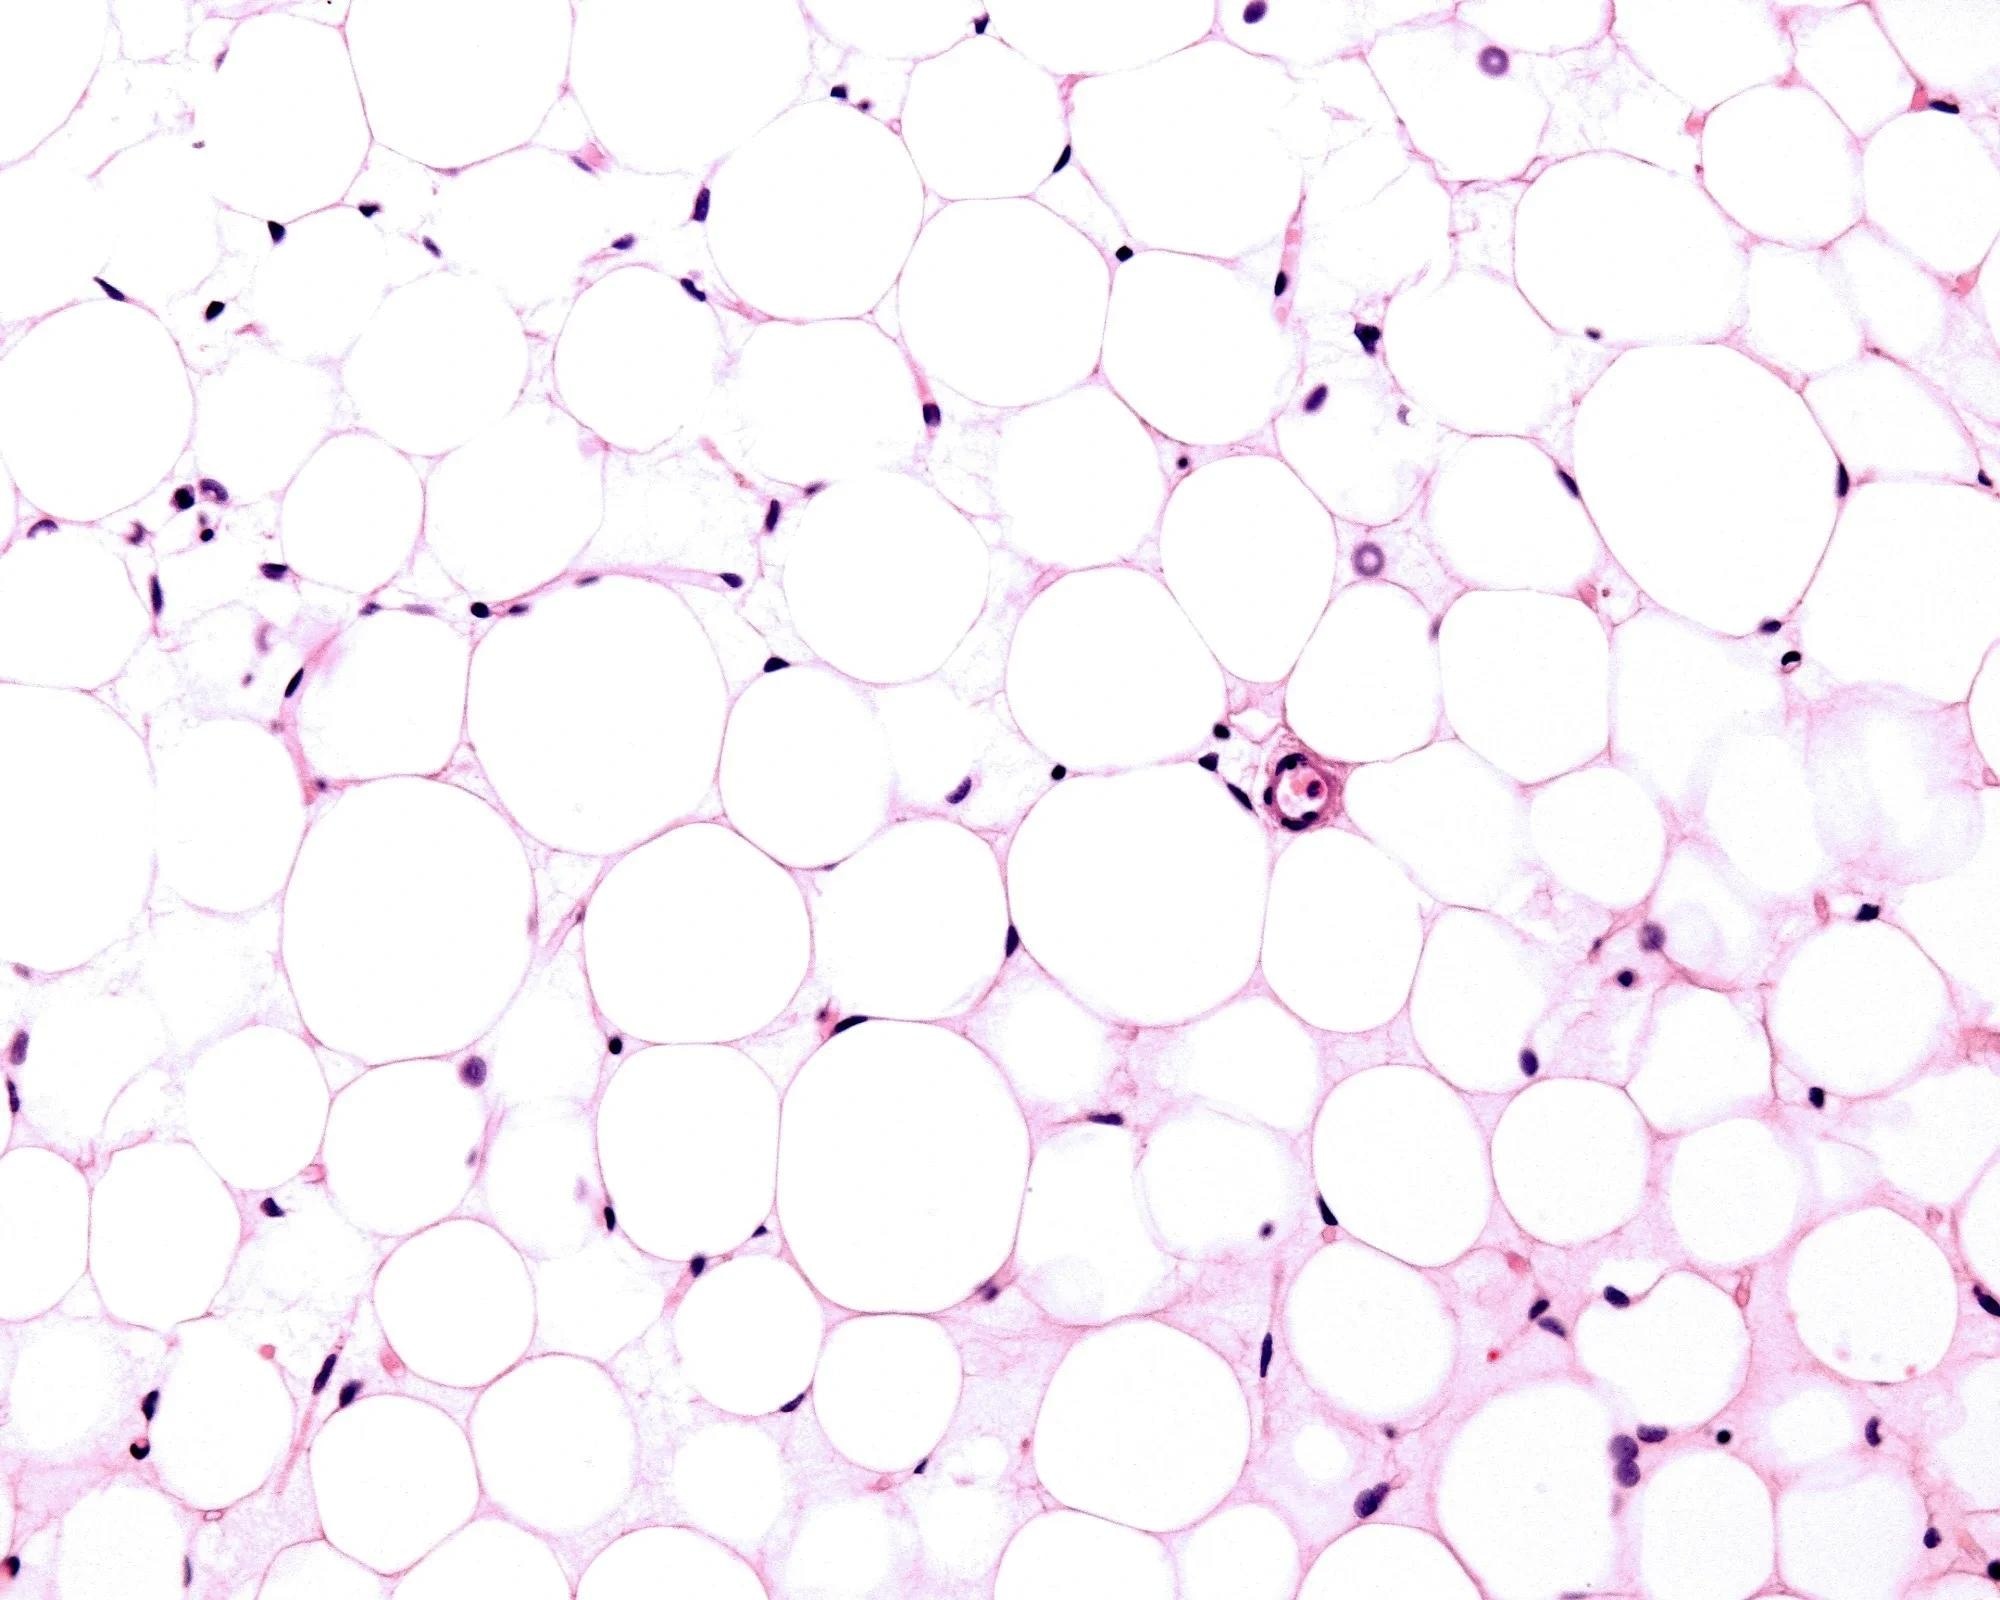

Adipose tissue biology and memory

Recent research has identified obesogenic memory within adipose cells and tissue. Even after significant weight loss, adipocytes may retain specific epigenetic markers and chromatin structures that keep the cells primed for metabolic responses to environmental changes.6

Cellular mechanisms of regain

Retained epigenetic markers, particularly in genes associated with lipid uptake and inflammation, remain accessible for transcription. Upon re-exposure to a high-calorie environment, these adipocytes may activate lipid-storage pathways more readily than adipocytes that have never been exposed to obesity.6

Immune cells, such as CD4+ T cells, within adipose tissue may also retain a memory of obesity by secreting factors that suppress energy expenditure and promote storage.2